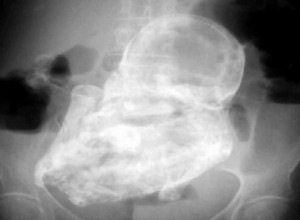

Doctors only discovered the rare medical phenomenon after ordering an X-ray that revealed the lithopedion, also called a “stone baby.” The woman is now expected to undergo surgery to remove it.

World News – An elderly Colombian woman was stunned when she went to the doctor for pelvic pain and was told the pain was caused by a 40-year-old “stone” fetus.The 82-year-old had been carrying the calcified four-pound fetus called a lithopedion for decades without realizing it, according to the Telegraph.